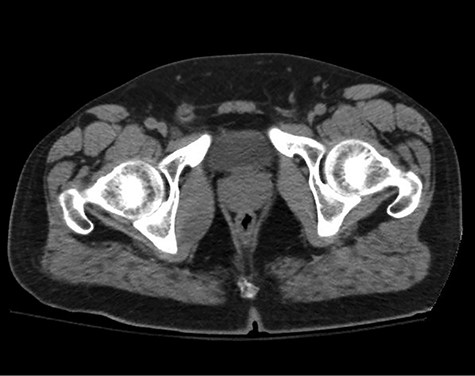

A healthy 47-year-old male with past medical history significant only for hypertension and nephrolithiasis presented to Englewood Health Medical Center in October 2019 with right flank pain radiating to the pubis, hematuria, hard stool with straining and fifteen pound weight loss over 6 months. On physical examination, multiple café au lait spots, small neurofibromas on his trunk and arms and axillary and inguinal freckling were observed. On CT scan, he was found to have a 10.1-cm soft tissue mass in the right hemipelvis and a nephroureteral stent with a 3-mm stone in the proximal right ureter (Fig. 1). Further history revealed the patient had a known pelvic mass discovered on CT approximately 10 years prior (Fig. 2), which was again observed on CT in June 2019 during a hospitalization for nephrolithiasis at Hackensack University Medical Center (Fig. 3); he had been lost to follow-up.

HUMC 6/1/19: 9.7 × 6.3 × 7.5-cm-sized right pelvic wall soft tissue mass.